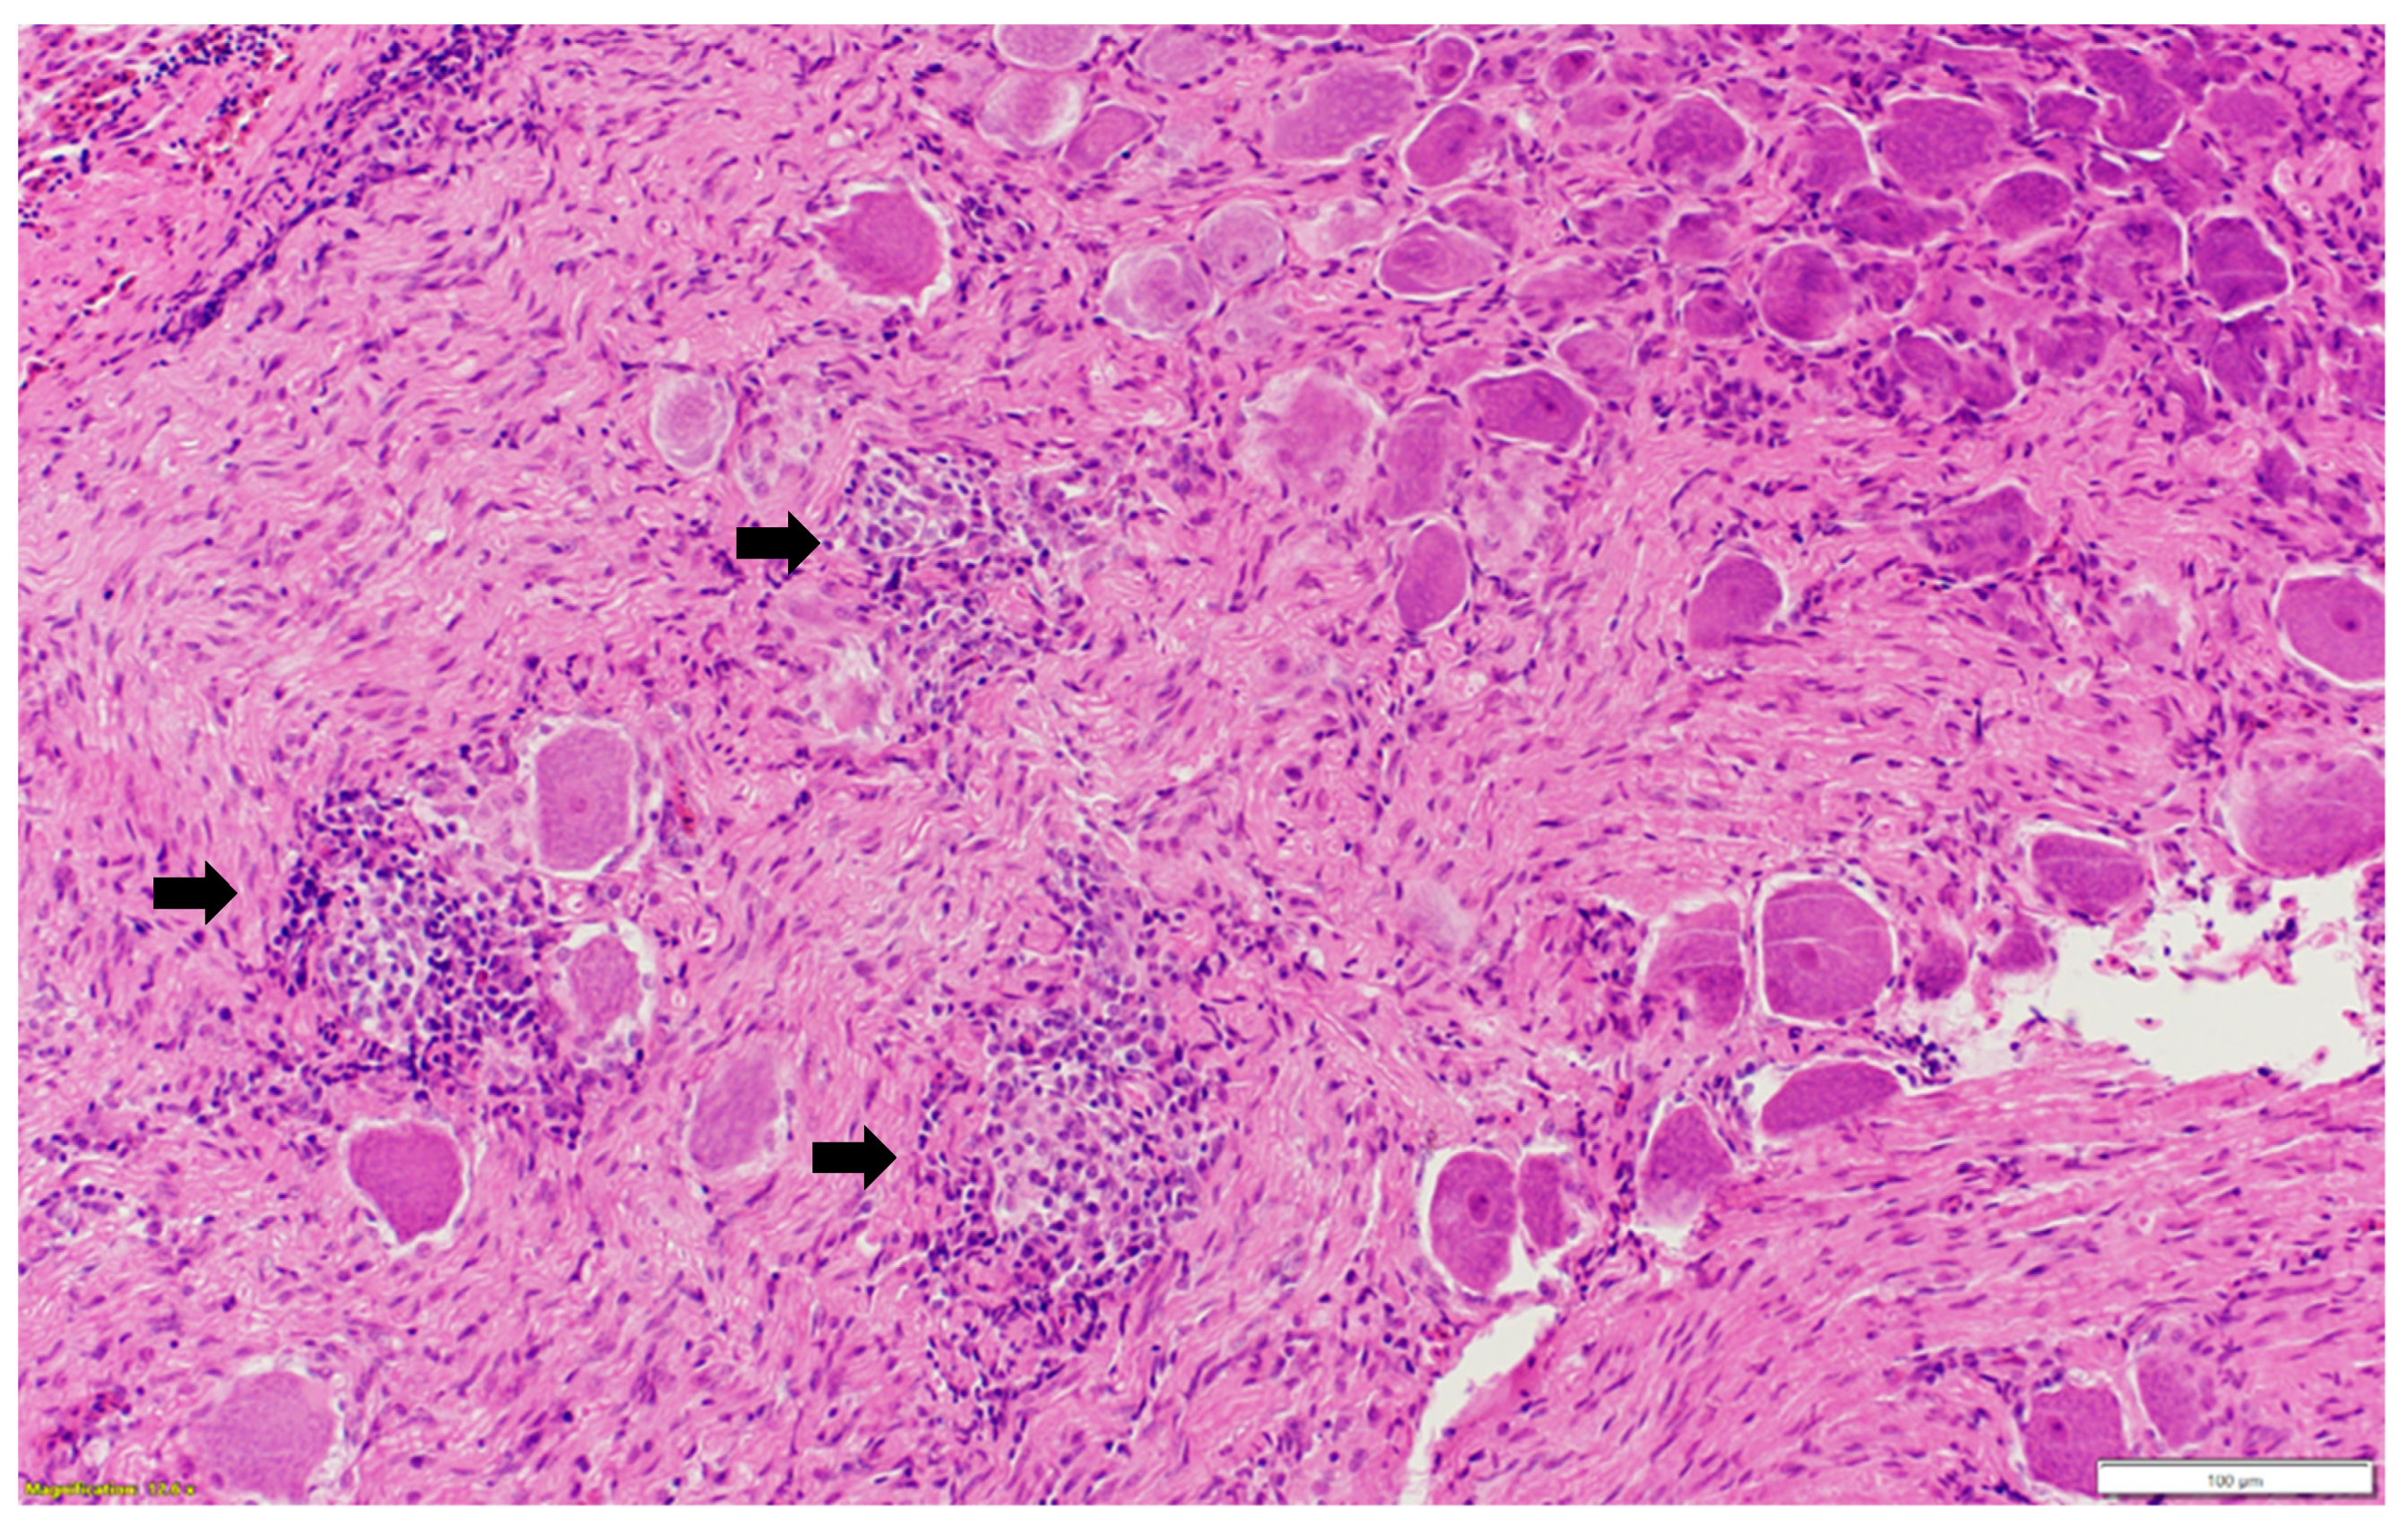

Microscopic examination of different brain, spinal cord, peripheral nerves, and ganglions sections revealed multifocal areas of lymphoplasmacytic and histiocytic infiltrates, indicating encephalitis (Figure 1) in the cerebral white matter, thalamus, hippocampus, and medulla oblongata close the ventricular space. The inflammatory cells around the vessels (perivascular cuffing) as well as around the neurons (satellitosis and neuronophagia) resulted in several neuronal degeneration and central chromatolysis (Figure 2). The gray matter in the spinal cord had multifocal lymphoplasmacytic infiltrates, indicating myelitis (Figure 3). In addition, there was mild to moderate multifocal ganglioneuritis in the pelvis ganglions (Figure 4).

Figure 4.

Multifocal inflammatory cellular infiltration (black arrow) among the ganglionic neurons (ganglioneuritis) in the pelvic ganglion. Paraffin-embedded tissue was stained with hematoxylin and eosin.